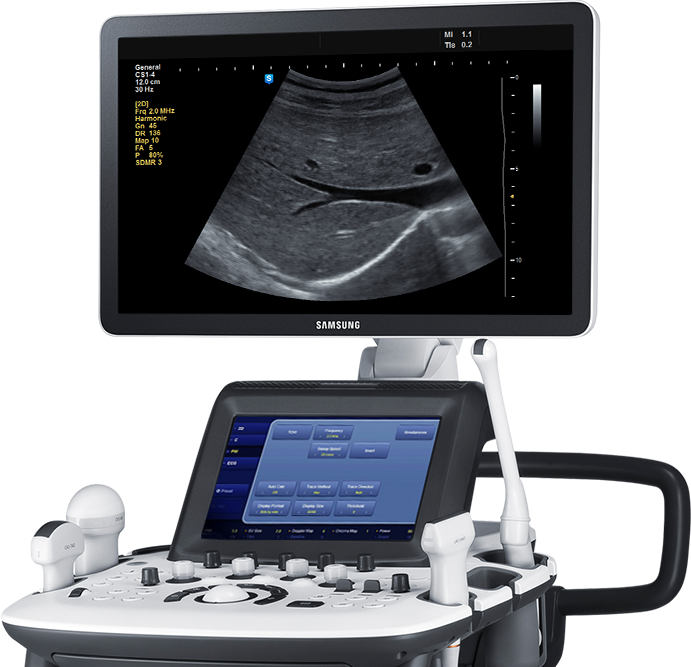

Utilizamos equipamentos novos e modernos, de última geração, com altíssima qualidade de imagem, permitindo exames de excelente acurácia diagnóstica.

Hoje, com os atuais equipamentos móveis e de alta resolução espacial, utilizando ondas sonoras de alta frequência, com múltiplas e variadas aplicações, a ultrassonografia permite a visualização de diversos órgãos e estruturas corporais sem radiação e sem necessidade do paciente entrar em equipamentos fechados, com notória vantagem para pacientes com claustrofobia.